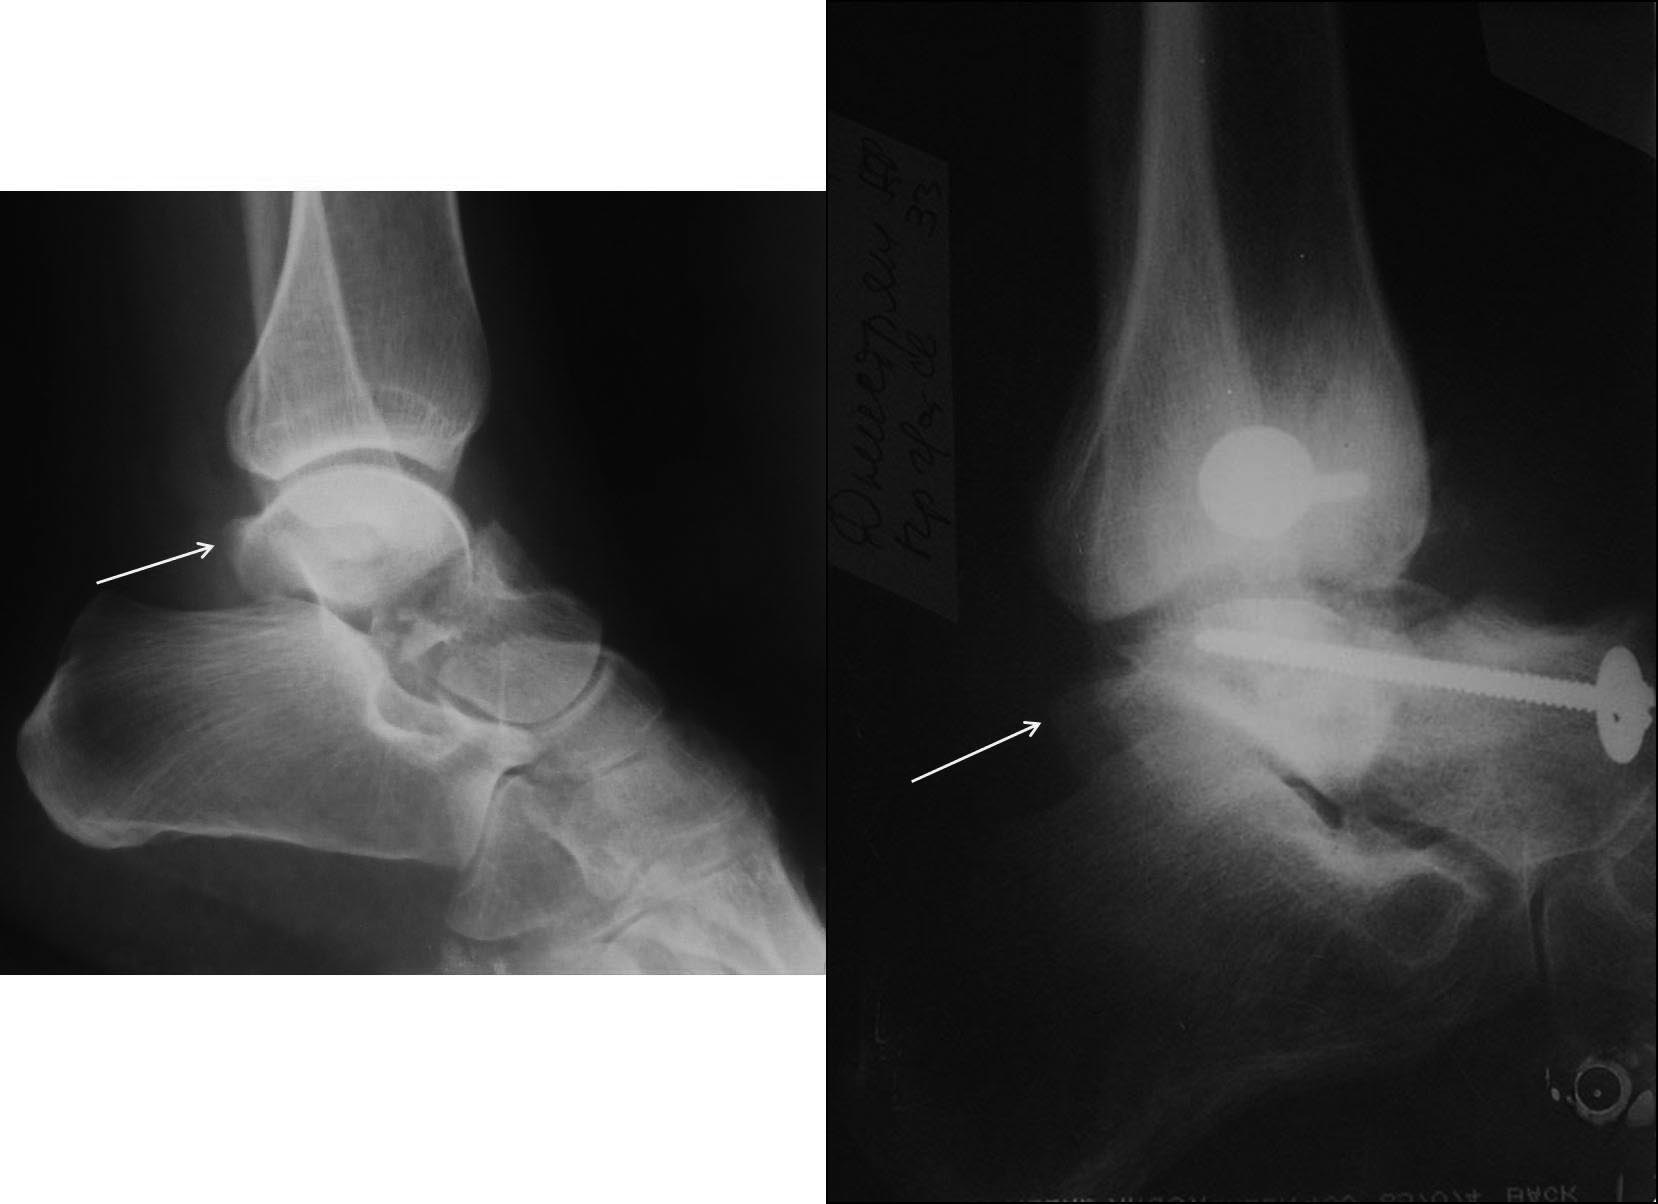

Во вложении похожий случай, оперированный 10 дней назад (с послеоперационными снимками). Для сравнения стрелками на двух рентгенограммах показан нависающий над пяточной костью вывихнутый фрагмент таранной кости. На компьютерной томограмме видно гораздо лучше. Так что о живом подтаранном суставе при сохраняющемся подвывихе говорить не приходится. Кстати, остеотомия внутренней лодыжки в такой ситуации - нормальный этап доступа, который должен планироваться до операции, а не быть следствием "тяжелой репозиции". Сейчас же, судя по плотности проксимального фрагмента, нужно исключать асептический некроз таранной кости и ее несращение. От этого будет зависеть тактика. Без КТ не обойтись. Во всяком случае, артродез голеностопного сустава при несросшейся разрушающейся таранной кости точно не будет правильным решением.